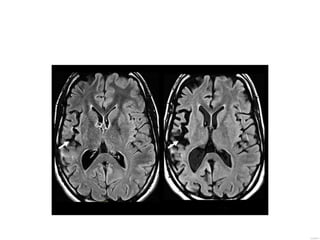

Imaging Approximately one third may show bilateral T2 hyperintense

affect temboral lobe, basal ganglia and thalmi

Imaging • Acute: hyperintensity subcortical region of the affected

hemisphere, often with severe edema.

• chronic stage: there is atrophy of the affected hemisphere

Imaging Progressive hemiatrophy